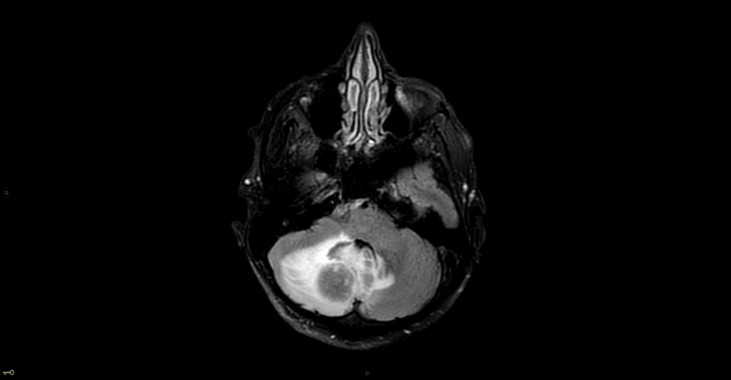

Métastase cérébelleuse droite